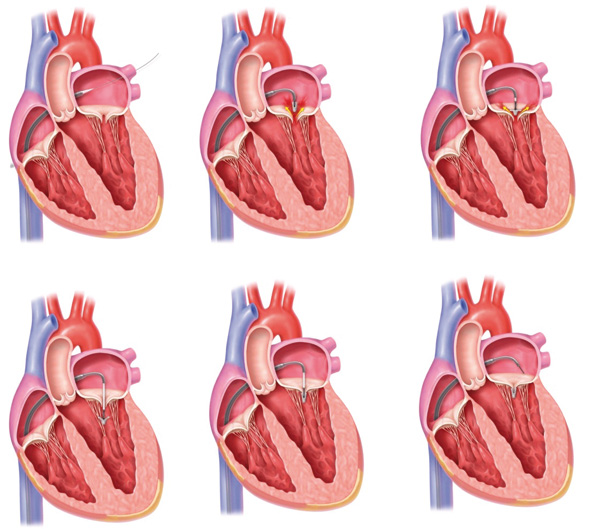

L’intervention consiste à introduire par la veine fémorale un cathéter qui sert de guide au dispositif dans la veine cave inférieure jusqu’à l’oreillette droite. Là, via une ponction au travers du septum inter-auriculaire, le médecin accède à l’oreillette gauche où il peut positionner le clip au-dessus de la valve mitrale, face au flux de la régurgitation mitrale. Le clip est alors placé exactement là où s’initie la fuite, entre les feuillets de la valve mitrale. La fermeture du clip permet de rapprocher les feuillets et de réduire la fuite. Lorsque le contrôle échographique indique un résultat satisfaisant, le clip est largué et le cathéter retiré. «?L’intervention est longue. Il faut compter environ quatre heures pour parvenir à attraper correctement deux feuillets asymétriques avec un clip symétrique, expliquent Adeline Guenat et Béatrice Toublanc, manipulatrices en électroradiologie médicale, qui jouent un rôle important dans l’intervention?: Nous nous chargeons de positionner le patient et le dispositif, qui doit rester parfaitement immobile et exactement à la même distance du cœur pendant toute la durée de l’examen. Une fois réalisée cette installation rigoureuse, le manipulateur est responsable pendant toute l’intervention du matériel spécifique et complémentaire.?»